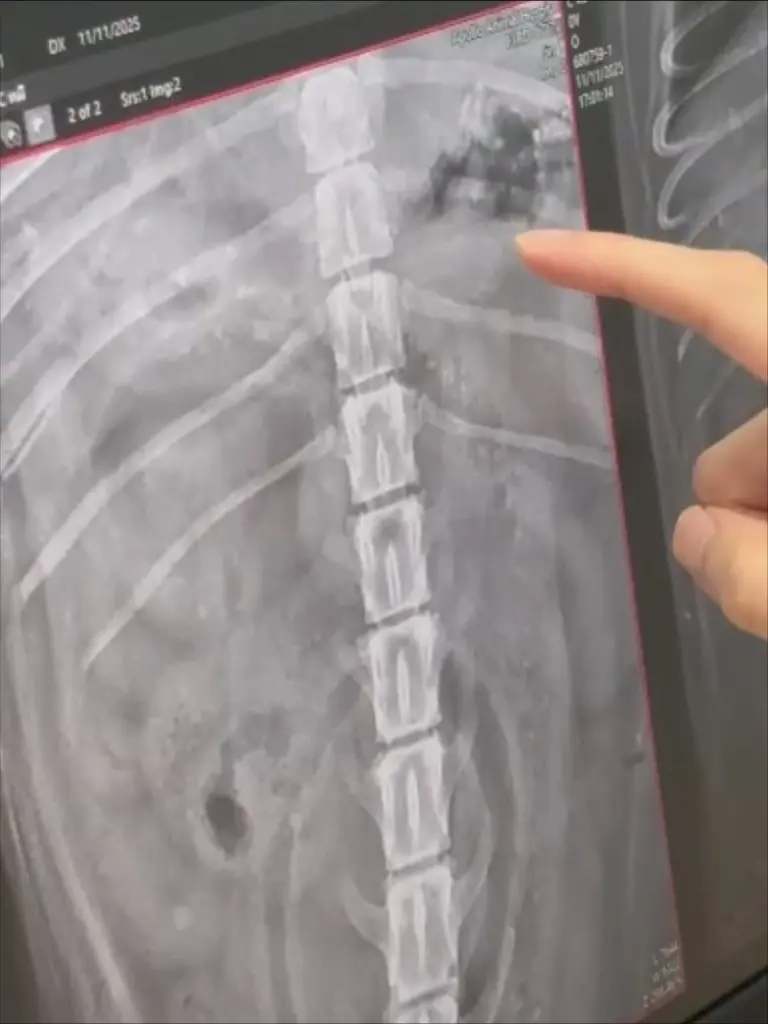

โดยโบกี้เผยว่าในตอนแรกเข้าใจว่าน้องหมีอาจมีปัญหาระบบทางเดินอาหาร เนื่องจากอายุมากแล้ว แต่เมื่อพาไปพบสัตวแพทย์และตรวจอย่างละเอียด ทั้ง X-ray, ส่องกล้อง และอัลตราซาวด์ กลับพบว่าในกระเพาะของน้องมี เศษสิ่งแปลกปลอมลักษณะแข็งคล้ายกระดูก ปูน และไม้ กระจายอยู่เต็มกระเพาะอาหาร

แต่หลังจากทานอาหารเปียกยี่ห้อหนึ่ง ก็มีอาการอาเจียนหนักมากกว่า 10 ครั้ง”🔸 “คุณหมอทำการล้างท้องแล้ว แต่ยังมีเศษสิ่งแปลกปลอมหลงเหลือในท้อง